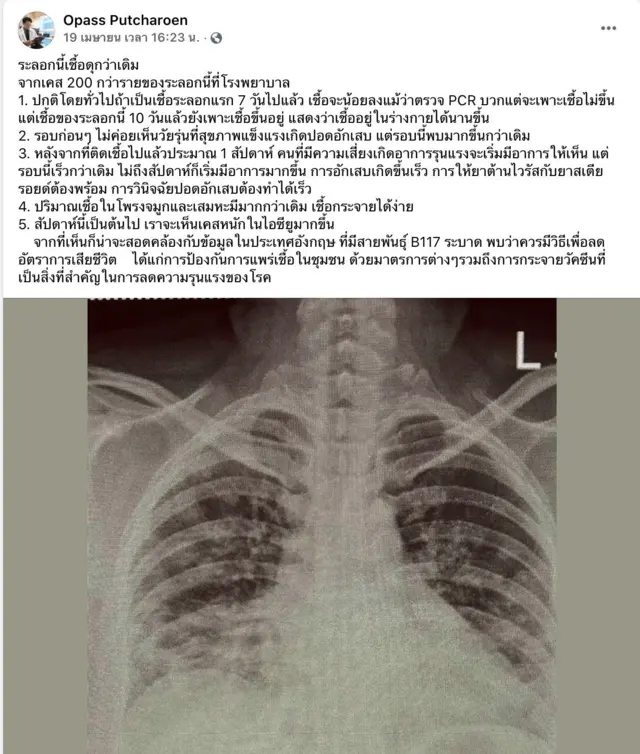

สอดคล้องกับความเห็นของ ผศ.นพ. โอภาส พุทธเจริญ ภาควิชาอายุรศาสตร์ คณะแพทยศาสตร์ จุฬาลงกรณ์มหาวิทยาลัย หัวหน้าศูนย์ความเป็นเลิศทางการแพทย์ โรคอุบัติใหม่ด้านคลินิก โรงพยาบาลจุฬาลงกรณ์ สภากาชาดไทย ที่ระบุผ่านเฟซบุ๊กเมื่อ 19 เม.ย. ว่า "ระลอกนี้เชื้อดุกว่าเดิม" และคาดว่าจะเห็น "เคสหนักในไอซียูมากขึ้น" โดยอ้างอิงข้อมูลจากผู้ป่วยกว่า 200 รายที่เข้ารักษาตัวที่โรงพยาบาล พบว่า เชื้ออยู่ในร่างกายได้นานขึ้น, ใช้เวลาไม่นานอาการก็มากขึ้น, เชื้อกระจายง่ายขึ้น ฯลฯ

เขายังระบุไว้ตอนหนึ่งว่า "มาตรการต่าง ๆ รวมถึงการกระจายวัคซีนที่เป็นสิ่งที่สำคัญในการลดความรุนแรงของโรค"

ที่มาของภาพ, Opass Putcharoen/FB